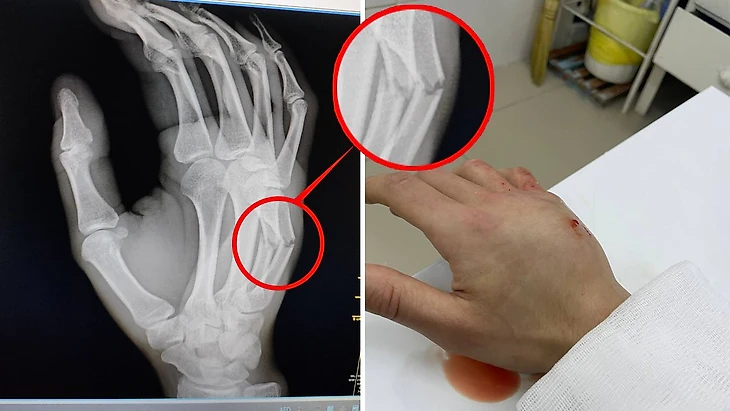

У Логи перелом четвертой и пятой пястной кости

У защитника 2Drots диагностирован перелом четвертой и пятой пястной кости.

Футболисту наложили гипс, сообщил доктор 2Drots Георгий Малякин.